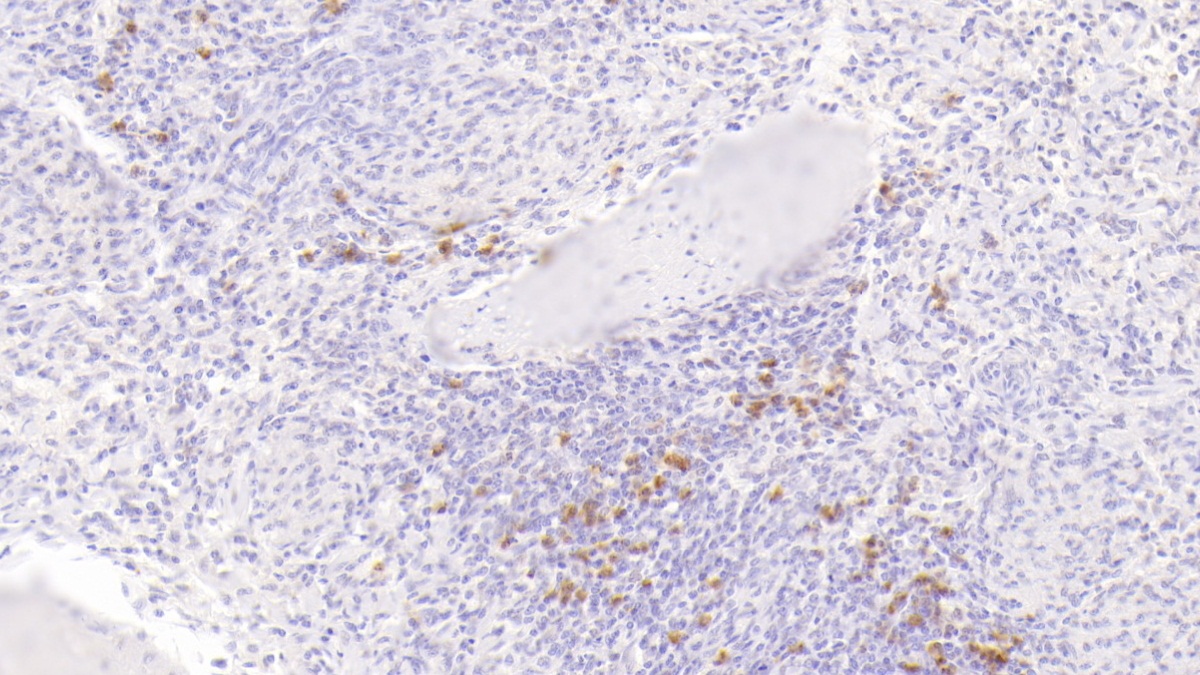

Polyclonal Antibody to S100 Calcium Binding Protein A9 (S100A9)

Product No.: PAB793Hu01

Organism species: Homo sapiens (Human)

Monoclonal Antibody to S100 Calcium Binding Protein A9 (S100A9)

Product No.: MAB793Hu22

Organism species: Homo sapiens (Human)